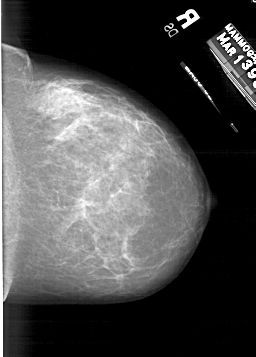

A_1217_1.RIGHT_CC

RIGHT_CC LINES 6061 PIXELS_PER_LINE 4336 BITS_PER_PIXEL 12 RESOLUTION 43.5 NON_OVERLAY